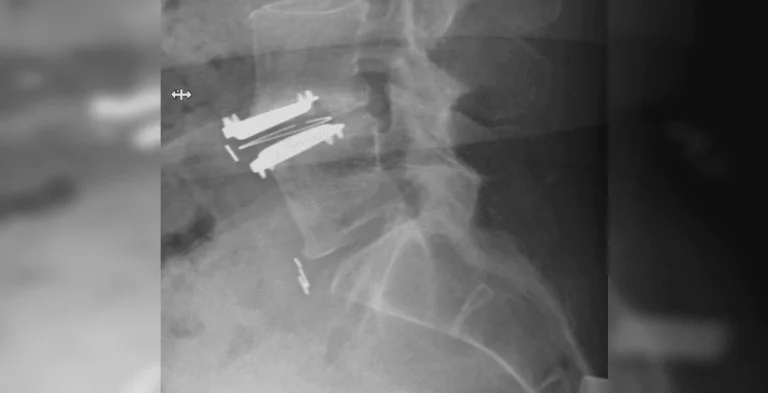

X-ray of a spine with metal screws and plates inserted.

Excessive Scar Tissue

X-ray of a neck showing metal screws and plates in the cervical spine.

Additional Surgery Likely

Side-by-side spinal X-rays showing vertebrae with surgical screws inserted.

Failed Back Surgery & Chronic Pain

Procedure fails to resolve pain, leading to failed back surgery syndrome and lifelong suffering.